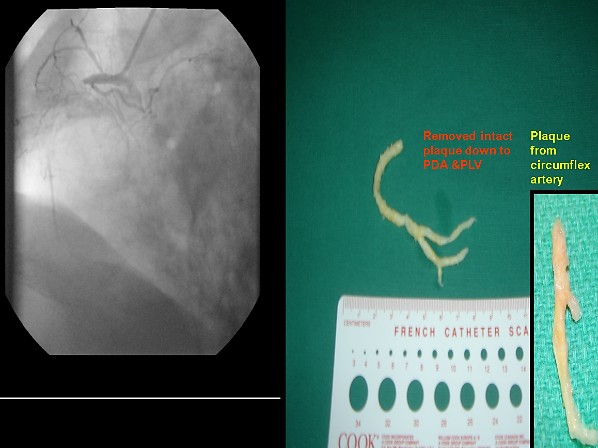

جراح القلب الدكتور عبدالإله مرشد يستاصل تكلس الشرايين التاجيه بالقلب جراحيا